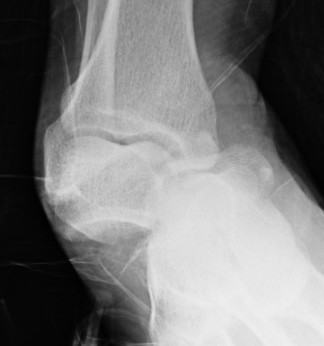

Lateral subtalar dislocation with fracture of the lateral malleolus

2. Lateral

- calcaneum dislocated laterally

- high energy trauma

- often associated with fractures

- can be difficult to reduce due to incarceration of tibialis posterior and FDL